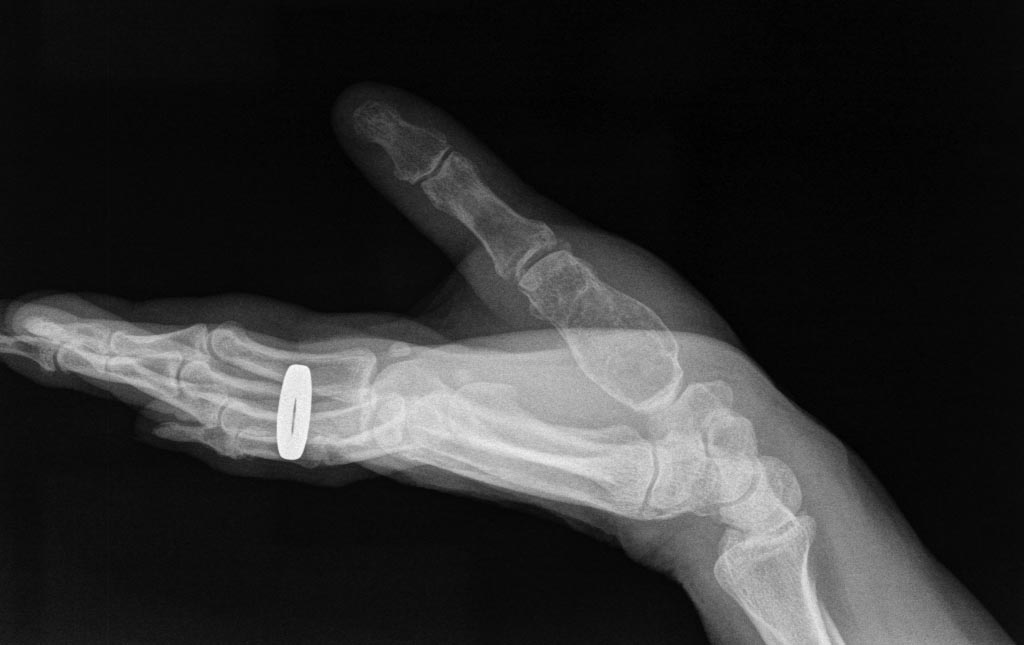

Re: Опухоль 1 пястной кости.

Есть несколько вариантов: энхондрома, гигантоклеточная опухоль, аневризмальная киста, метастаз и еще несколько крайне редких опухолей.

Энхондрома обычно не болит; разве что только при патологическом переломе. Снимок очень похож на энхондрому.

Гигантоклеточная опухоль и аневризмальная киста: обычно развиваются более динамично, чем энхондрома.

пациентки 51г вр.дерматолог.Боли около года.Рентгенографию сделала первый раз.

Как по мне - очень похоже на энхондрому по характеру кальсификации. Если боль будет продолжаться, операция при энхондроме будет очень эффективной, но я все же постарался бы понаблюдать.

А что, только боль мешает пациентке жить? Надо довести больную до патологического перелома (от компактного слоя почти ничего не осталось!) или до того, что опухоль полностью "съест" всю кость, включая суставные поверхности?

Я тоже не уверен, что это - точно ОБК. На первом снимке - не видно, а на втором просматриваются "мыльные пузыри". Если интраоперационная диагностика будет больше указывать на энхондрому, то можно такую большую полость заместить чем угодно. А если будет все-таки ОБК, то я бы выполнил сегментарную резекцию и заместил дефект малоберцовой костью.

На мой взгляд, больше похоже на ОБК. Дефект лучше заполнить аутокостью.

Это эн-хондрома. Внутриочаговая резекция и костная пластика